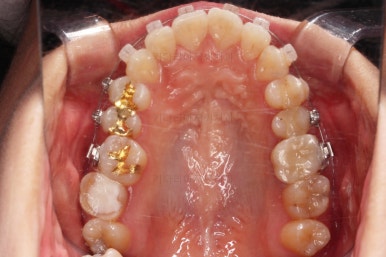

마찬가지로 초진 시 입안의 모습입니다.

입안 사진을 보니 문제점이 보이죠.

바로 어금니가 없는 상태였습니다.

물론 치열도 그리 많이 삐뚠 편은 아니고, 치아가 없으니 심플하게 임플란트를 해 넣으면 되지 않겠나 라고 생각할 수 있지만요.

나이도 많이 어리시고, 임플란트를 한다는 심리적 저항감도 있었고요.

한 번 임플란트를 해 넣으면 교정치료가 매우 힘들어진다는 점과 겸사겸사 돌출감도 개선하고자 하는 의지가 있으셔서 임플란트 없이 사랑니를 살려서 어금니 대신 쓰는 부산사랑니교정 치료를 해보기로 했습니다.

초진 시 파노라마 X-ray 사진인데요.

어금니 하나는 이미 뺀 상태이고요.

추가로 2개 더 어금니 상태가 좋지 못한 상황이었습니다. 물론 윗니 화살표 치아는 신경치료 해서 살려 쓸 수도 있지만 발치를 하기로 결정했습니다.

아래쪽도 어금니를 발치해야 된다는 점.(큰 어금니를 뽑으면 기간이 일반 교정보다 오래 걸리는데 어차피 아래도 큰 어금니 발치가 기간상의 손해는 없다는 점)

윗니도 작은 어금니든 뭐든 발치가 필요했던 상황에서 작은 어금니보다도 장기적인 예후가 불량하다고 판단된 점.

마침 해당 부위 사랑니도 있어서 마치 큰 어금니가 2개가 남는 것처럼 구성할 수 있는 점.

등등의 사실로 인해 발치를 부담없이 결정했고요.

발치교정 및 큰어금니 발치 자리는 뒤쪽 사랑니도 앞으로 끌고 오면서 공간을 없애주기로 했습니다.

겸사겸사 돌출입도 개선하고요.